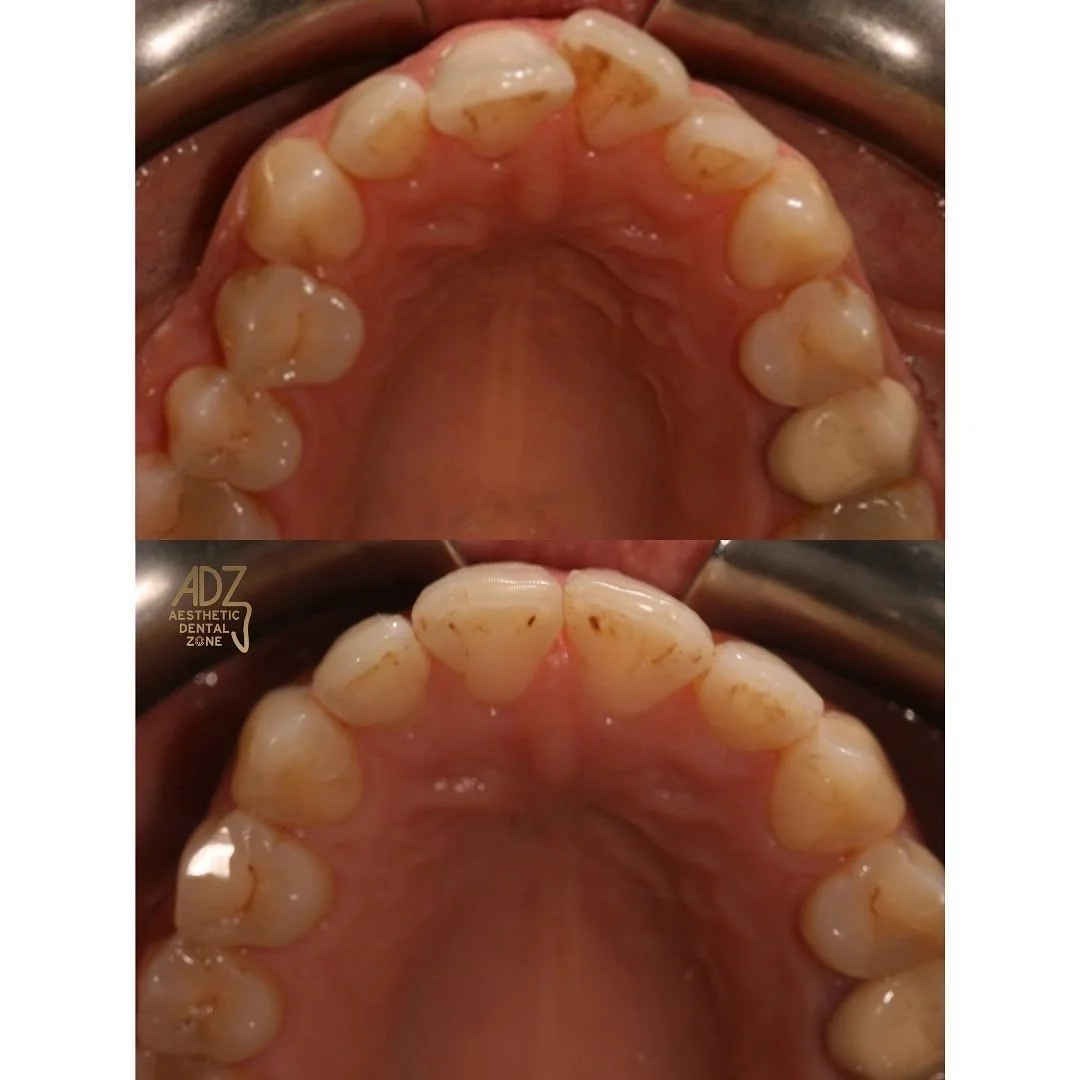

Fixed Appliance - Braces

You've most likely heard of braces. they're the most common fixed appliance. They consist of bands, wires, and brackets. How do they work? The bands are the anchors held in place around your teeth. Brackets are attached to the front of your teeth. Arch wires connect the brackets to the bands. Tightening the archwires puts pressure on your teeth, slowly moving them towards their target position. Braces are usually adjusted monthly and are worn for a few months to a few years.

Looking for an alternative to metal braces? Here at Aesthetic Dental Zone, we offer Clear Aligner or also known as Invisalign. A simple and invisible cosmetic solution to achieving the smile you desire. Avoid fixed appliances (braces) and realign your teeth with a set of our aligners. They are comfortable, clear and easy to wear.